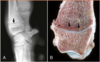

Describe the lesions that come with metaphyseal osteopathy?

initially: bilaterally symmetrical suppurative and fibrinous osteomyelitis of metaphysis of multiple long bones, separation (fx) of metaphysis due to inflammation/necrosis has a "double growth plate" appearance (double radiolucency parallel to physis) chronically: periosteal new bone

You see this lesion in a 4 month old Bernese Mountain Dog. What is it?

Metaphyseal osteopathy